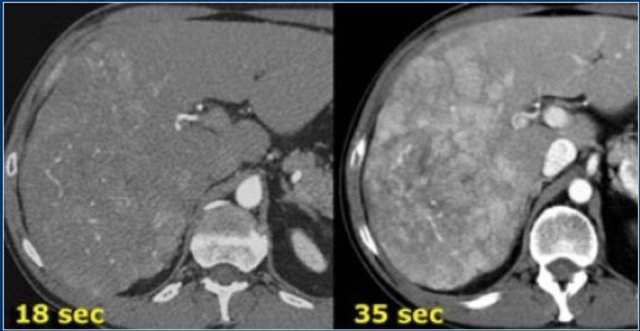

The CT-images show an early arterial phase in comparison to a late arterial phase.

The CT-images are of a patient who underwent two phases of arterial imaging at 18 and 35 seconds.

In the early arterial phase we nicely see the arteries, but we only see some irregular enhancement within the liver.

In the late arterial phase we can clearly identify multiple tumor masses.